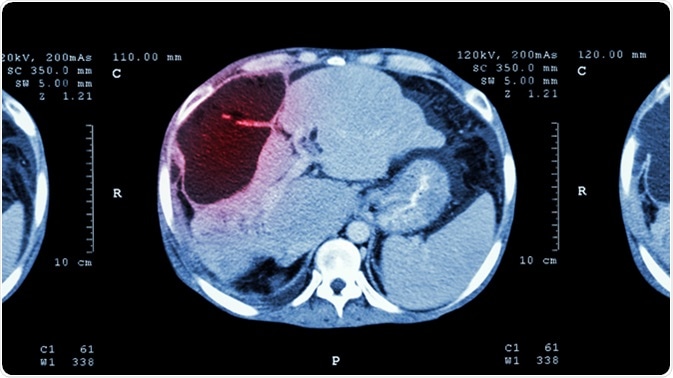

CT scan of upper abdomen : show abnormal mass at liver (Liver cancer). Image Credit: Puwadol Jaturawutthichai / Shutterstock